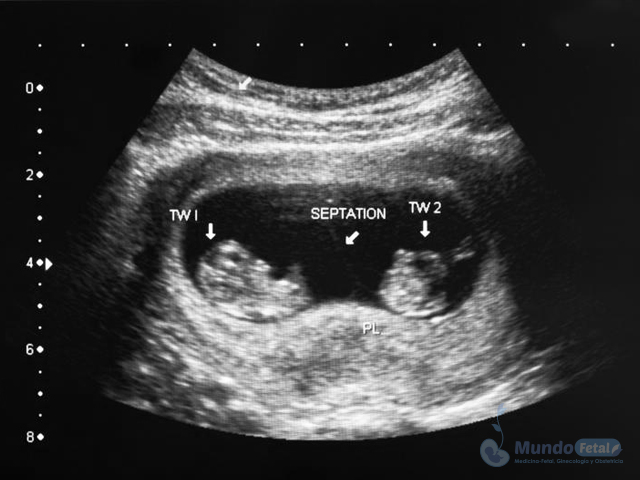

Es esencial detectarlo desde el primer trimestre (especialmente 11-13.6 semanas de gestación) con la intención de conocer el número de bebes, cuántas placentas y bolsas amnióticas, ya que el seguimiento de estos es distinto, esto por los riesgos que conllevan de presentar alguna alteración propia de estos embarazos, indicativos de una vigilancia estrecha y estudios complementarios, durante toda la gestación.

• Descartar o confirmar oportunamente riesgos y anomalías, sugerentes de vigilancia y estudios complementarios.

• Tratamiento oportuno

• Evitar complicaciones propias de estas gestaciones.